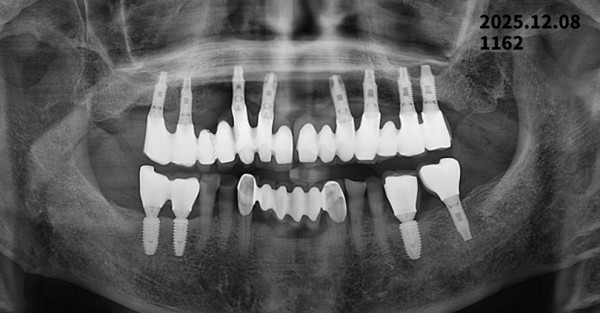

2011년 임플란트 식립 후 2025년 정기검진

2011년 임플란트 식립 후 약 14년이 경과한 2025년 정기검진 파노라마 X-ray를 통해

임플란트 주위 **치조골 변화**를 추적 관찰한 사례를 소개해 드리겠습니다.

2025년: 정기검진 파노라마 촬영

???? 상악(윗턱) 임플란트 변화

2011년과 비교했을 때 2025년 영상에서

* 임플란트 나사산 주변 골 접촉 상태가 전반적으로 잘 유지

* 임플란트 목 부위에서 경미한 치조골 흡수는 관찰되나

→ 장기 사용 임플란트에서 흔히 나타나는 생리적 변화 범위

여러 개의 임플란트가 보철물로 연결된 구조로,

저작력 분산이 비교적 안정적으로 이루어진 상태로 판단됩니다.

???? 하악(아랫턱) 임플란트 변화

* 좌·우 하악 후방 임플란트 모두

2011년 대비 치조골 높이 변화가 크지 않음

* 임플란트 주위에 염증을 의심할 만한

뚜렷한 방사선 투과성 소견은 보이지 않음

???? 임플란트 주위염(peri-implantitis)을 강하게 의심할 소견은 없는 상태입니다.

???? 종합 평가

✔ 임플란트 식립 후 14년 이상 경과한 상태임을 고려하면 매우 안정적인 결과

✔ 임플란트 탈락이나 급격한 골 소실 소견 없음

✔ 정기적인 관리가 잘 이루어진 사례로 판단됩니다